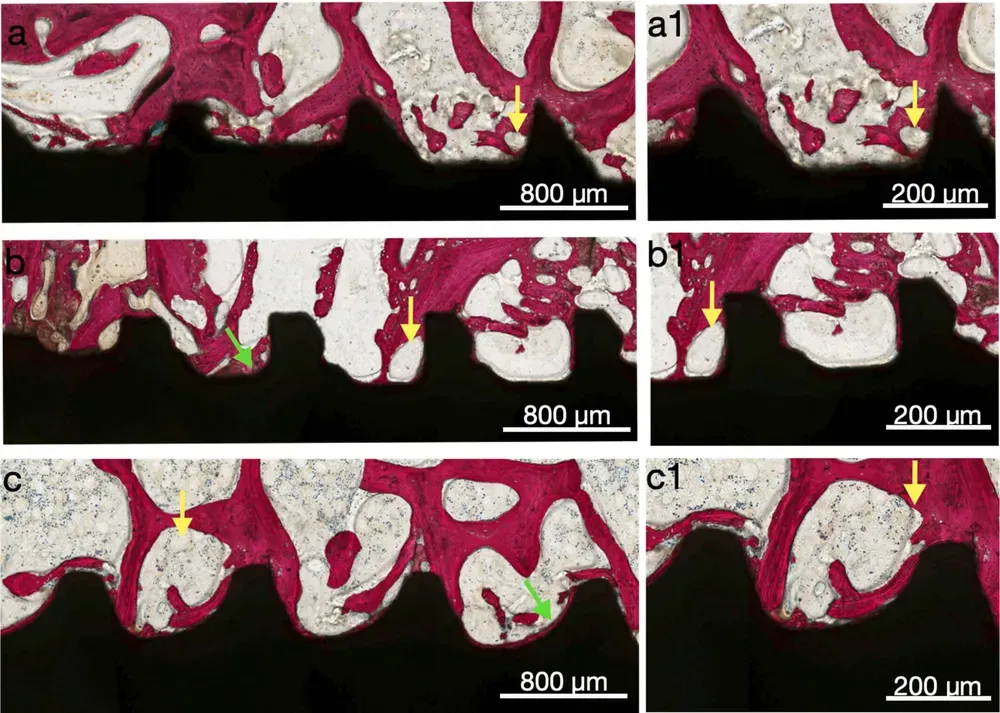

Le immagini sottostanti, tratte dal sopracitato articolo, dimostrano a tre e sei settimane come le camere di guarigione stimolano visibilmente la neoformazione ossea al loro interno (tratto da Benalcázar-Jalkh et al., 2025, licenza CC 4.0)

Gehrke et al. hanno mostrato che gli impianti con healing chambers (le “camere di guarigione” di cui sopra), anche in osso a bassa densità, presentano maggiore quantità di osso sulla superficie dopo il test di pull-out rispetto ai design convenzionali (Gehrke, Scarano et al., 2021). In uno studio su tibia di coniglio, gli stessi autori hanno confermato che le camere di guarigione producono valori di ossificazione superiori rispetto ai filetti convenzionali a “V” e a filetto quadrato (Gehrke et al., 2019).

Le spire larghe e con passo aumentato creano le cosiddette “camere di guarigione” — veri e propri polmoni biologici dell’osso. In quegli spazi il sangue si raccoglie, il coagulo si stabilizza più agevolmente rispetto a una superficie liscia, e l’osteogenesi inizia subito dopo l’inserimento.

Nessuna compressione. Nessuna ischemia. Solo coagulo, proteine, globuli bianchi, e osteoblasti.